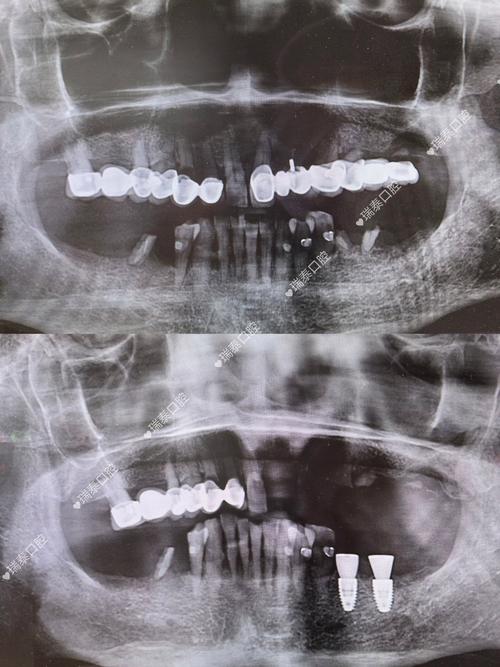

CT在种牙过程中的具体作用主要体现在以下几个方面:一是评估骨量条件,缺牙后牙槽骨会逐渐吸收萎缩,不同患者的骨量差异较大,通过CT可以精确测量缺牙区骨的高度、宽度、密度,判断是否满足种植体的植入要求,如果骨量不足,还可以提前规划植骨手术,确保种植体有稳定的骨结合基础,二是定位重要解剖结构,下颌骨内有下颌神经管,上颌骨内有上颌窦,这些结构周围是神经和血管密集的区域,种植体一旦损伤可能导致下唇麻木、上颌窦炎等问题,CT能清晰显示这些结构的边界和位置,帮助医生设计安全的种植路径和角度,三是指导种植方案设计,基于CT的三维数据,医生可以进行数字化模拟种植,确定种植体的最佳植入位置、角度和长度,选择合适的种植体型号,对于复杂病例,还可以利用CT数据制作3D打印手术导板,术中将导板放置在口腔内,引导种植体精准植入,减少手术创伤,缩短手术时间,四是术后评估,种植手术后,通过CT复查可以观察种植体的位置是否理想,与周围重要结构的关系是否正常,以及骨结合情况,为后续的修复治疗提供依据。

目前种牙前常用的CT检查主要是锥形束CT(CBCT),与传统螺旋CT相比,CBCT具有辐射剂量低、成像速度快、分辨率高、成本较低等优势,更适合口腔科检查,不同类型的CBCT在成像范围和精度上略有差异,医生会根据患者的具体情况选择合适的检查方式,单颗牙缺失可能只需拍摄局部区域,而全口种植则需要拍摄全颅颌影像,以下为不同口腔检查影像技术的对比: